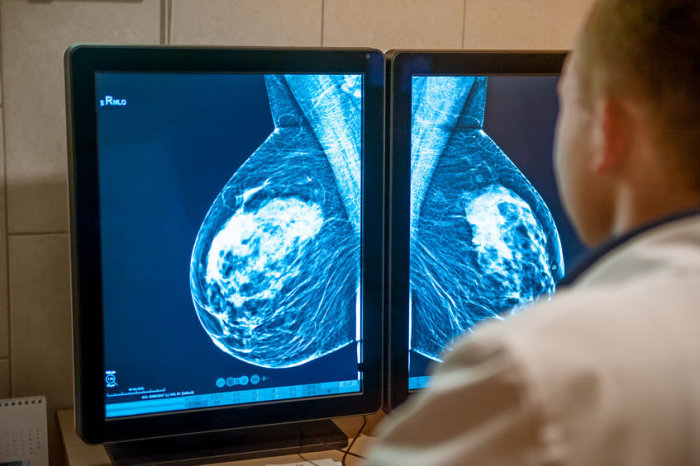

Uma empresa que presta serviços de plano de saúde foi condenada a pagar indenização de R$ 8 mil por negar exame a uma paciente com suspeita de câncer. A decisão é do juiz Jamil Amil Albuquerque, da 7ª Vara Cível de Maceió.

De acordo com os autos, o médico da paciente prescreveu o exame de mamotomia guiada por ressonância magnética com sedação venosa. A mulher, no entanto, foi surpreendida com a negativa do plano Bradesco Saúde, que alegou que o exame não está inserido no rol da Agência Nacional de Saúde Suplementar (ANS).

O procedimento, segundo a paciente, precisa ser feito para investigar a natureza de um nódulo em sua mama direita, assim como a evolução dos que já existem em sua mama esquerda. Reforçou ainda a necessidade da sedação durante o procedimento, por ter claustrofobia.